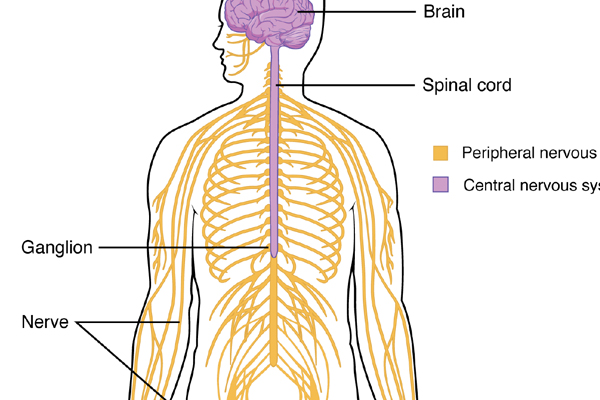

Neurological Disorders